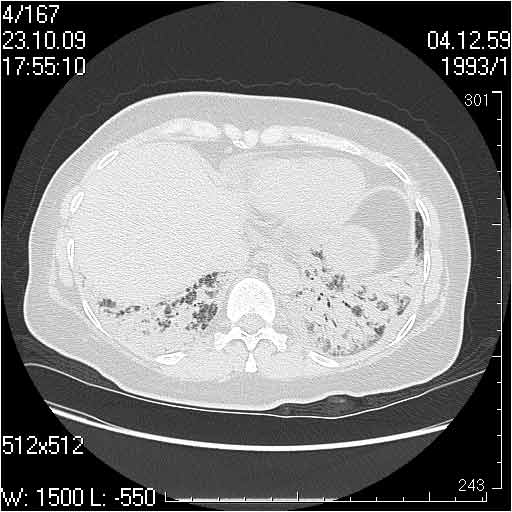

Случай №3

Женщина 51 год

Случай 3:смешанные изменения; подходят для интерстициальной пневмонии, тактика аналогична случаю 1.